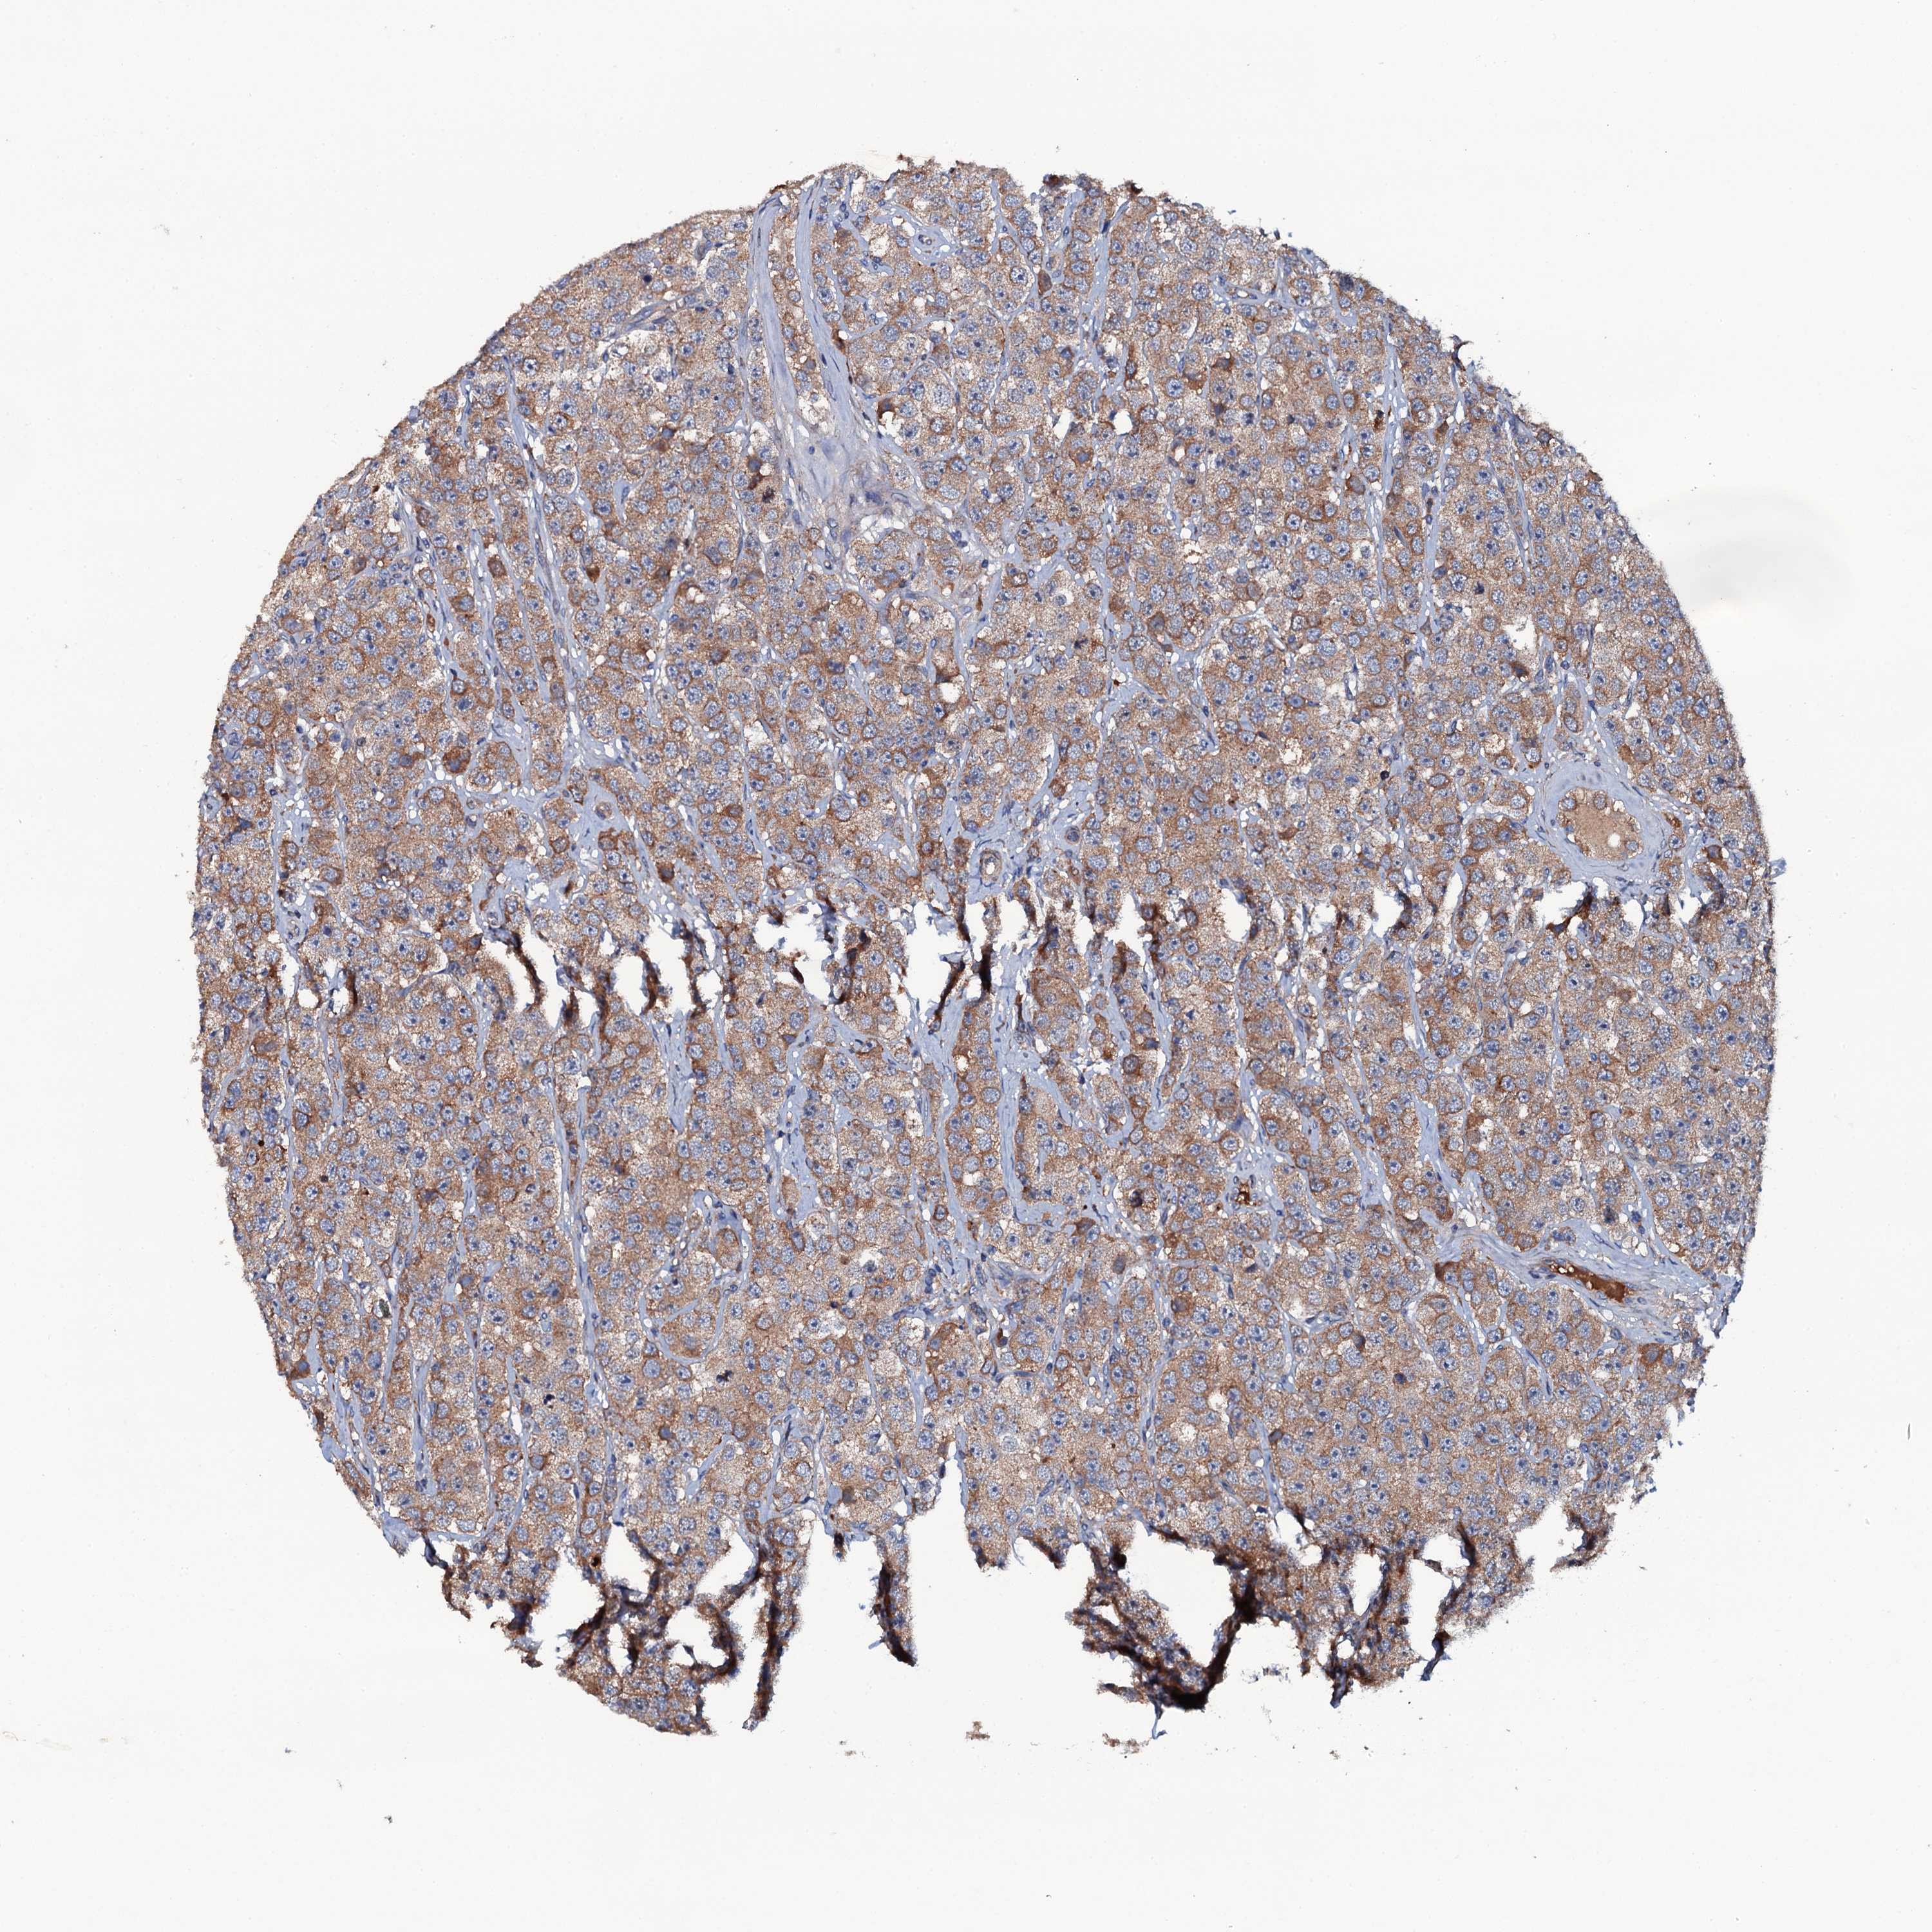

TESTIS CANCER - Protein expressioni

A mouse-over function shows sample information and annotation data. Click on an image to view it in a full screen mode. Samples can be filtered based on level of antibody staining by selecting one or several of the following categories: high, medium, low and not detected. The assay and annotation is described here.

Note that samples used for immunohistochemistry by the Human Protein Atlas do not correspond to samples in the TCGA dataset.

Antibody stainingi

Antibody staining in the annotated cell types in the current human tissue is reported as not detected, low, medium, or high, based on conventional immunohistochemistry profiling in selected tissues. This score is based on the combination of the staining intensity and fraction of stained cells.

Each image is clickable and will lead to virtual microscopy that enables deeper exploration of all samples and also displays staining intensity scores, fraction scores and subcellular localization as well as patient and tissue information for each sample.

Antibody HPA020873

Carcinoma, Embryonal, NOS

Seminoma, NOS